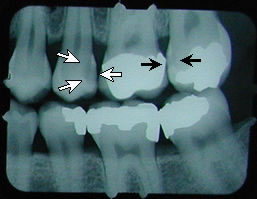

second cavity